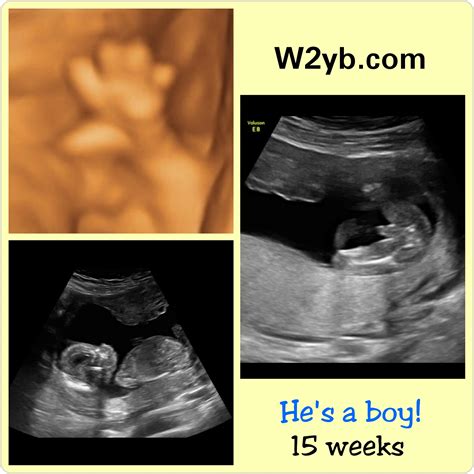

• Gender Determination: In some cases, the baby’s gender can be determined during this scan, although it is more reliably identified later in the pregnancy.

• Can I find out the baby’s gender?: While it is possible to determine the gender at 15 weeks, it is more reliably identified later in the pregnancy, around 18-20 weeks.

• 15 week gender scan

• 15 week ultrasound gender pictures

• 15 weeks ultrasound pictures